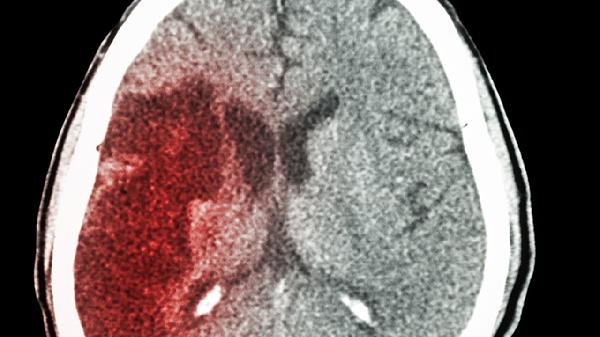

三、眼部症状与脑梗的关系

1、视网膜中风

视网膜中央动脉阻塞被称为"眼中风",与脑梗有相似的危险因素,但不等于脑梗。